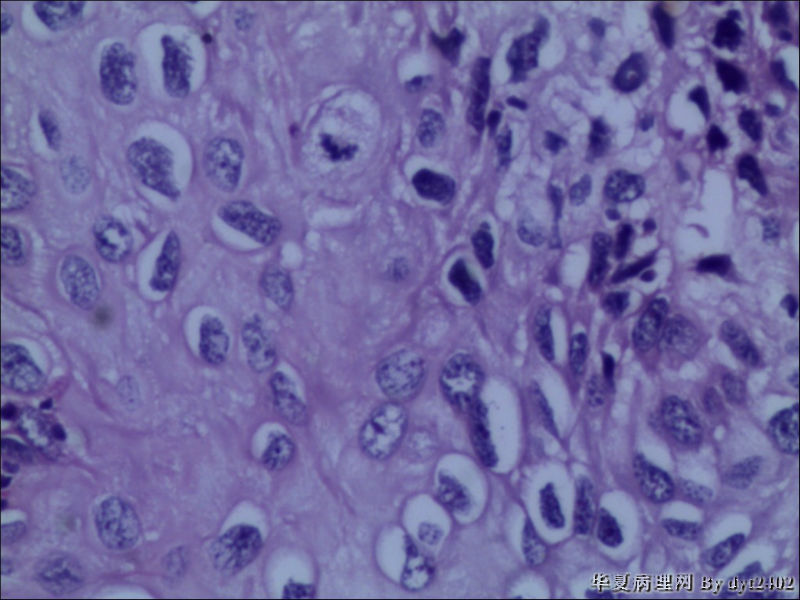

• 宫颈活检 其中一点较迷糊图1

图1

四点中三点是CIN iii,另一点怀疑有更重病变

这个病人是44岁,去年11月底阴道脱落细胞、TCT均见细胞异常,建议活检,病人犹豫,接着单位组织到外院体检时做阴道镜正常,后霉菌感染,此时宫颈未涂醋肉眼看还光滑,直至今年3月来做活检,事前做白带检查又见异常细胞,宫颈未涂醋见后上唇白上皮,涂醋酸后上下唇都有厚白上皮,镶嵌,夹活时上皮剥脱,未能夹到间质,阴道镜医生说至少有CIN III 到原位癌了。。镜下其中3点CIN III无疑,唯有9点处如6、7、11、14等所示结构,但我未见间质浸润,不能说是浸润癌,不知道有没基底细胞样鳞癌的可能,我发了个原位癌不除外深部有更重病变,。